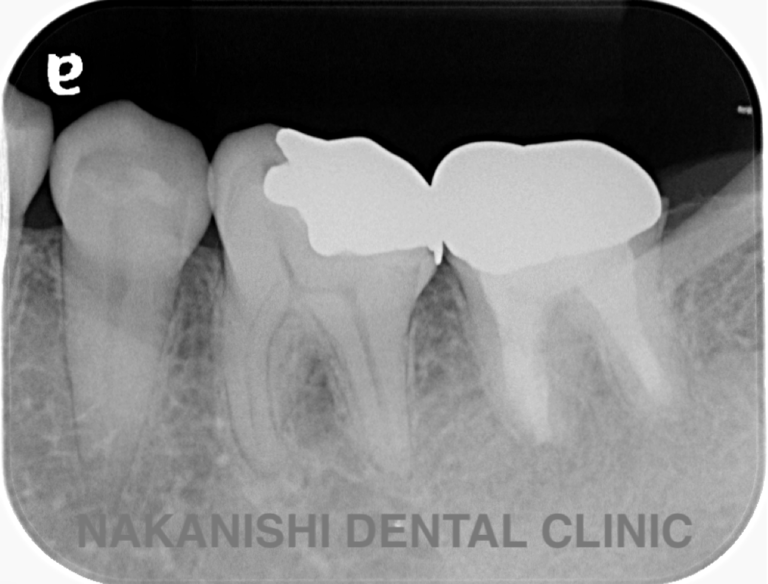

case 2.

治療前

治療後

| 主訴 | 左下歯ぐきの腫れ。 |

|---|---|

| 治療期間 | 約2か月 |

| 治療費 | 約1万5千円 |

| 治療内容 | ラバーダム、マイクロスコープ下にて根管治療を施術。 歯ぐきの腫れ、痛みや違和感が消失したため根管充填、支台築造(土台の製作)を行った。治療後の写真は矯正治療を行うことになったため仮歯を装着した状態。 |

| 治療のリスク | マイクロスコープやCTを使用し、可能な限り精密な根管治療を行っていますが、歯根の形態や病変の大きさ、過去の治療履歴などにより、治癒が得られない場合があります。また、治療後に再感染や歯根破折が生じることもあり、その場合は再治療や抜歯が必要となることがあります。 治療結果には個人差があり、すべての症例で同様の経過を保証するものではありません。 |